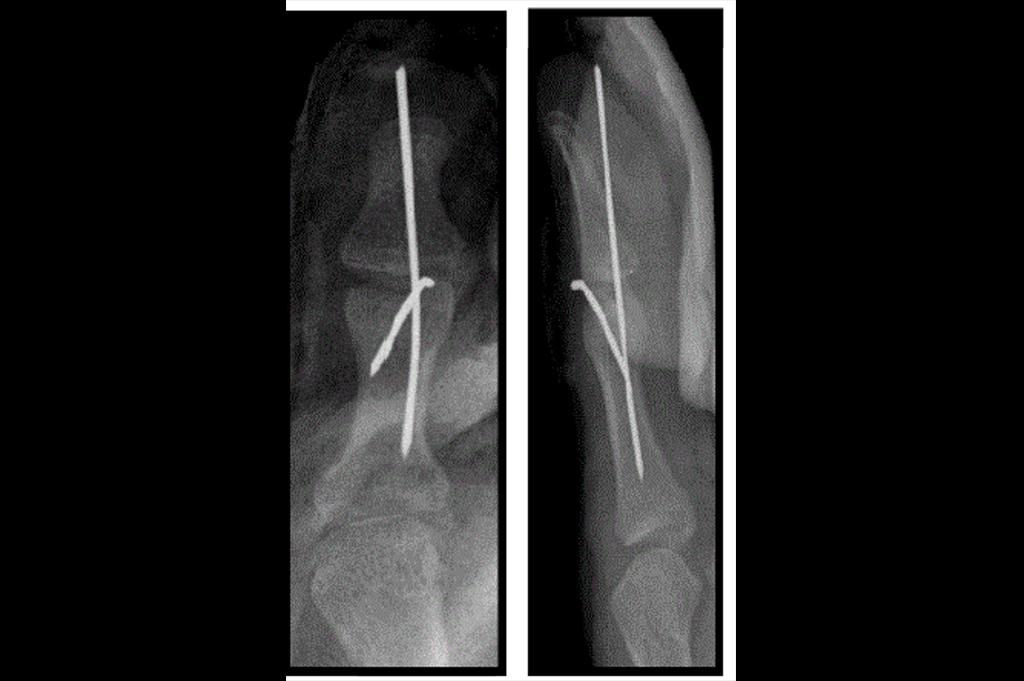

Mallet Finger